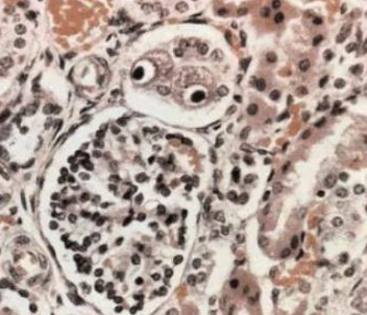

Cytomegalovirus (巨細胞病毒)

- Monocyte、Lymphocyte、Epithelial cell → Monocyte、Lymphocyte

- 編碼IL-10 的結構類似物

- 最常造成先天缺陷(Congenital defects)的病毒

- 一般人感染沒事

- 免疫低下

- 視網膜炎(retinitis):脈絡膜視網膜炎(chorioretinitis)

- Oral ulcer

- Owl’s-Eye inclusion body

- 通常是病毒複製、繁殖的地方

- 通常是病毒複製、繁殖的地方